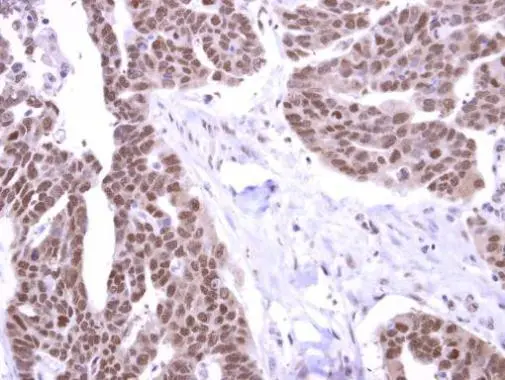

Anti-Stk31 antibody used in IHC (Paraffin sections) (IHC-P). GTX119718

GTX119718 IHC-P Image

Stk31 antibody detects Stk31 protein at cytoplasm and nucleus human on ovarian carcinoma by immunohistochemical analysis. Sample: Paraffin-embedded ovarian carcinoma. Stk31 antibody (GTX119718) dilution: 1:500.

Antigen Retrieval: Trilogy™ (EDTA based, pH 8.0) buffer, 15min